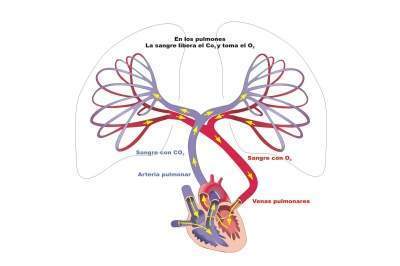

Los pulmones. Son órganos esenciales del aparato respiratorio, es el sitio en que se verifican las importantes funciones de la hematosis. En ellos la sangre recibe oxígeno desde el aire y a su vez la sangre se desprende de dióxido de carbono el cual pasa al aire. Este intercambio, se produce mediante la difusión del oxígeno y el dióxido de carbono entre la sangre y los alvéolos que forman los pulmones.

Los vasos del pulmón son unos funcionales por donde se realiza la hematosis y otros nutricios.

- Vasos de la hematosis: Son las arterias pulmonares y las venas pulmonares.

Las arterias pulmonares en numero de dos, una derecha y otra izquierda, se dirigen hacia el hilio, cruzando la cara anterior y luego la externa del tronco bronquial. Cada tronco arterial se ramifica como el bronquio correspondiente, de suerte que cada bronquio va acompañado de un ramo de la arteria pulmonar. Una vez llegado al lobulillo correspondiente, este ramo lo penetra, para capilarizarse en él. Excepción hecha de lo que se refiere a la mucosa de los más pequeños bronquios extralobulillares, la arteria pulmonar se distribuye exclusivamente por el epitelio alveolar.

Las Venas pulmonares proceden unas de los capilares alveolares, cuyos troncos venosos se reúnen en la periferia del lobulillo y de las redes capilares de las últimas ramificaciones bronquiales. A las venas precedentes se añaden ramillos venosos que toman origen en la pleura. Condensadas en troncos cada vez más voluminosos, únicos para cada ramo correspondiente de la arteria pulmonar, y ocupando en el bronquio la cara opuesta, las venas llegan al hilio; allí forman cuatro troncos, dos derechos y dos izquierdos, los cuales se abren en la aurícula izquierda.

Función respiratoria

Circulación pulmonar

El sistema arterial que irriga a los pulmones (arterias pulmonares y sus ramificaciones) sigue un trayecto paralelo al de las vías respiratorias, mientras que el sistema venoso es más variable y puede disponerse en diferentes trayectos.

En el pulmón derecho la vena pulmonar superior drena los lóbulos superior y medio, y la vena pulmonar inferior drena al lóbulo inferior.

En el pulmón izquierdo cada vena pulmonar drena al lóbulo de su mismo nombre. Hay que tener en cuenta que la circulación pulmonar presenta una peculiaridad con respecto al resto de la circulación sistémica, puesto que las arterias pulmonares aportan sangre poco oxigenada desde el ventrículo derecho, mientras que las venas pulmonares, tras el intercambio gaseoso en los alvéolos, aportan sangre oxigenada hacia la aurícula izquierda.